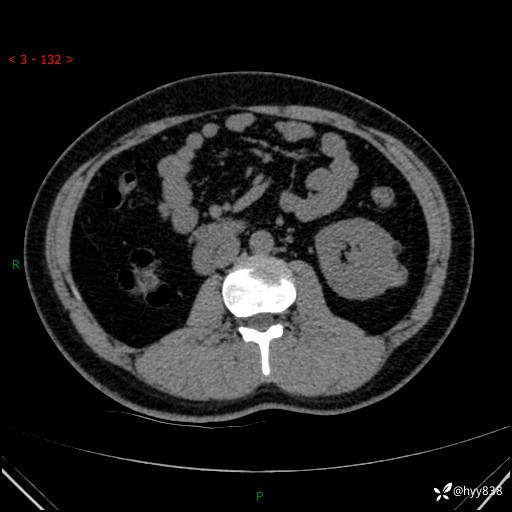

患者性别:男

患者年龄:28岁

简要病史:右肾肿瘤术后,常规复查

辅助检查:CT

临床诊断:右肾肿瘤术后

腹部CT+颅脑CT平扫